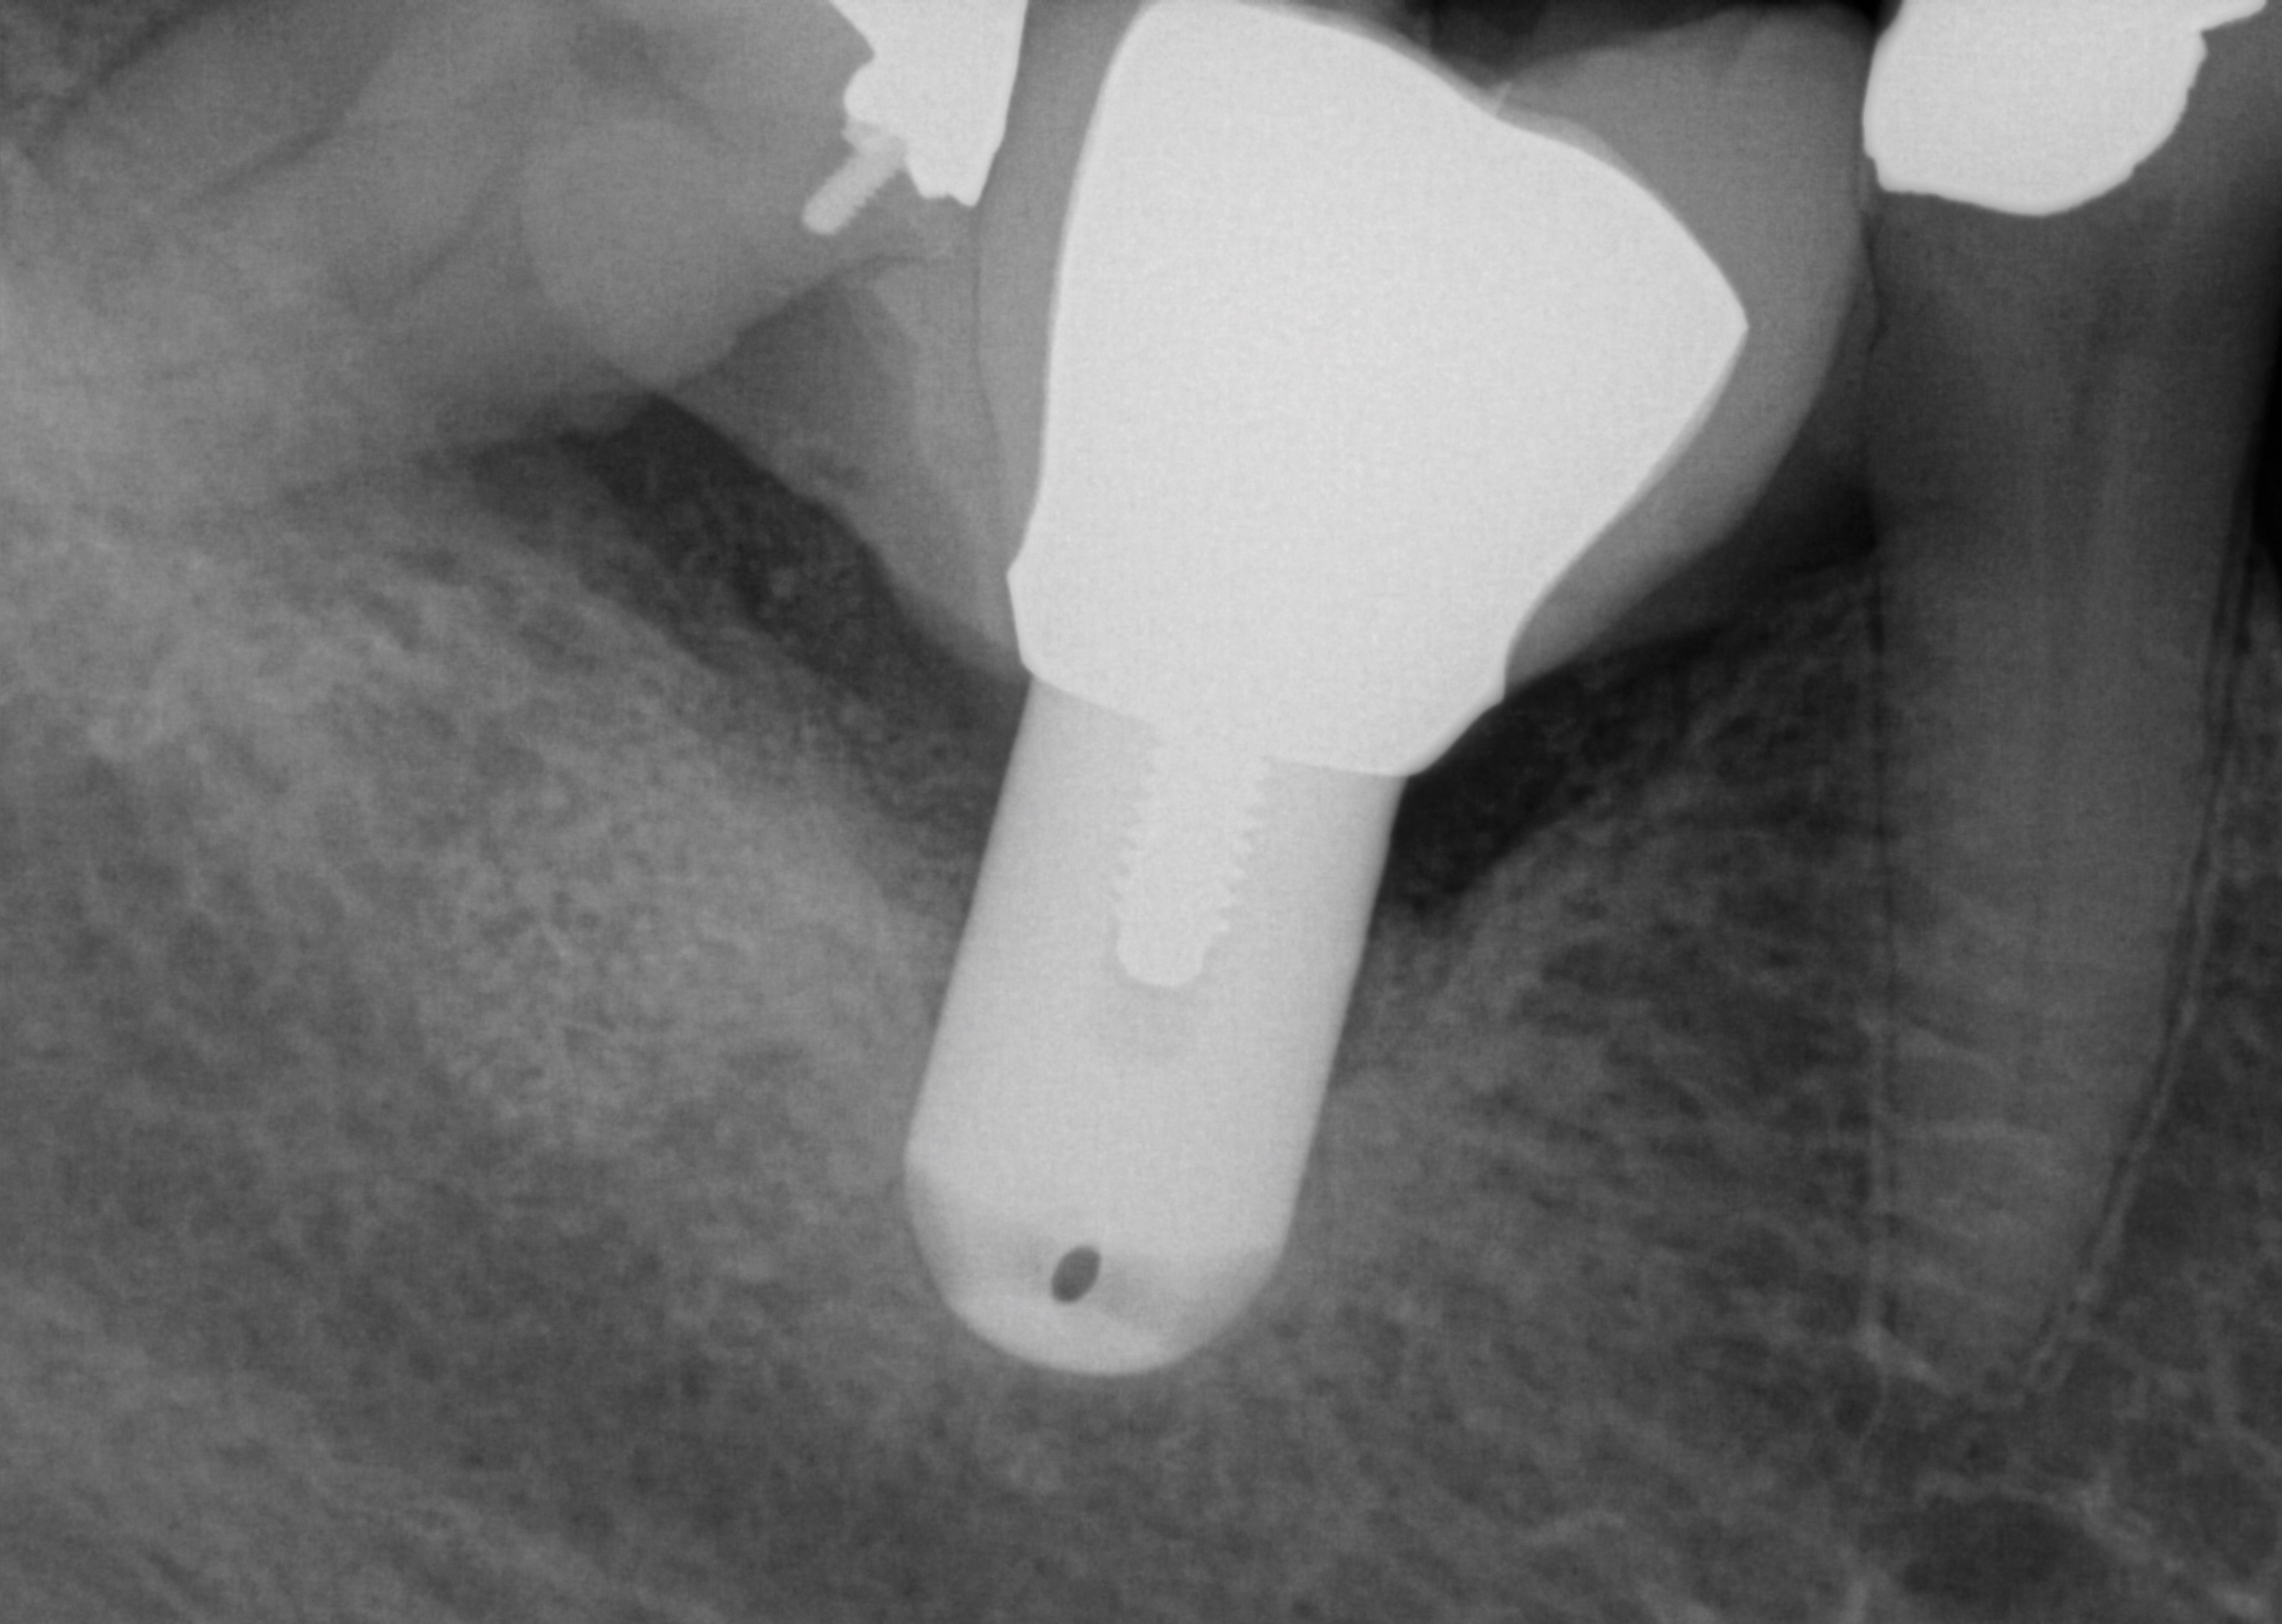

Fig 3. A patient presented with intense pain in tooth No. 31. A periapical radiograph demonstrated acute apical periodontitis. It was not possible to identify the extent of the periapical lesion with respect to the inferior alveolar canal.

Figure 3